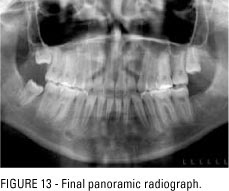

– Hình ảnh Xquang toàn diện, sọ nghiêng, sọ thẳng

Phim X quang toàn cảnh trước điều trị